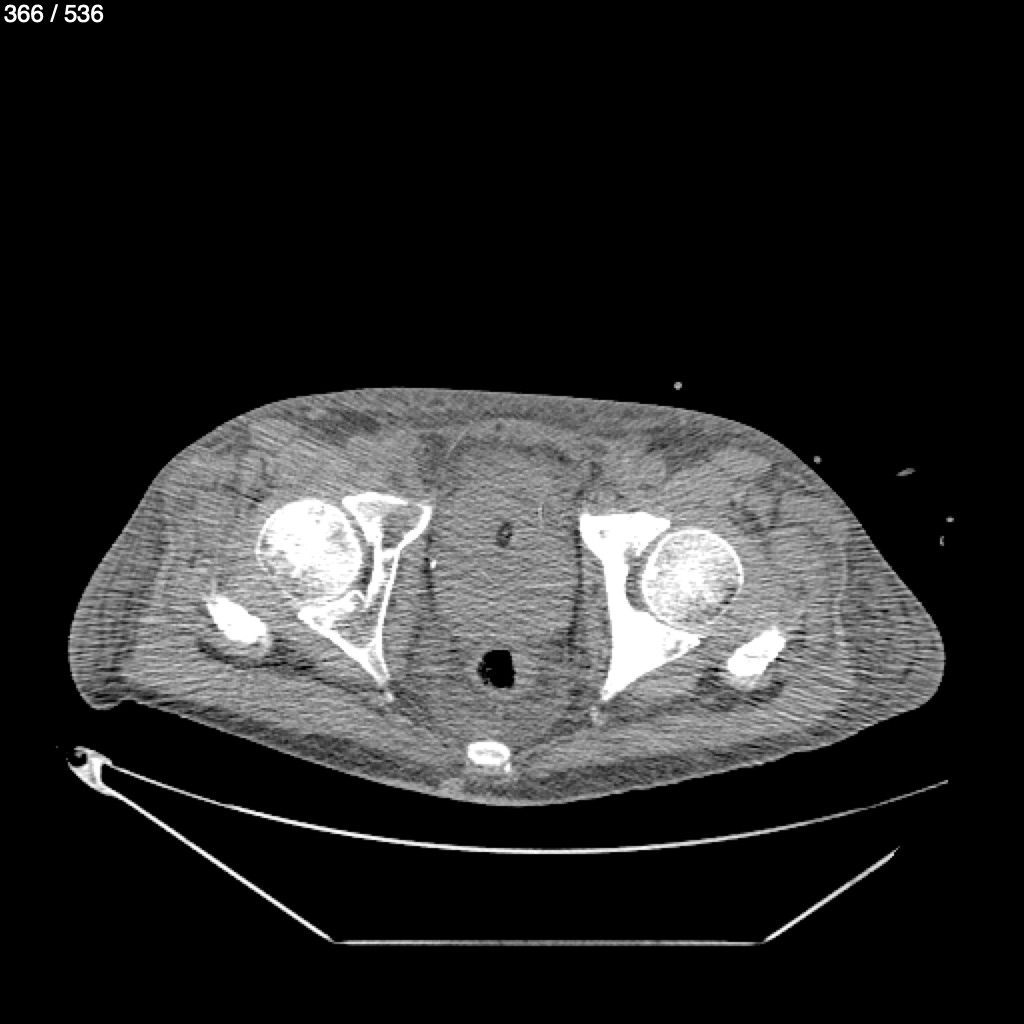

Angel Villalobos Palomeque 73 A - T.C Abdomen Simple